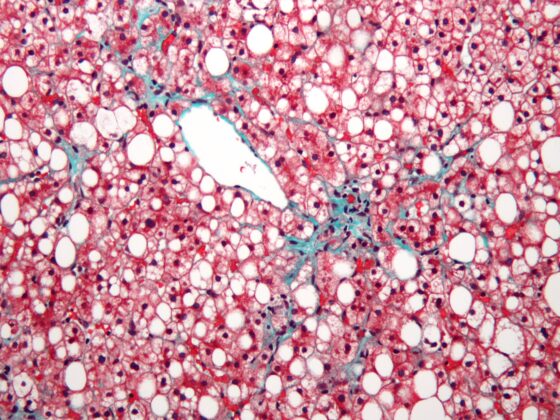

• Nicht-alkoholische Fettlebererkrankung (NAFLD)

Was sagt die aktuelle Leitlinie?